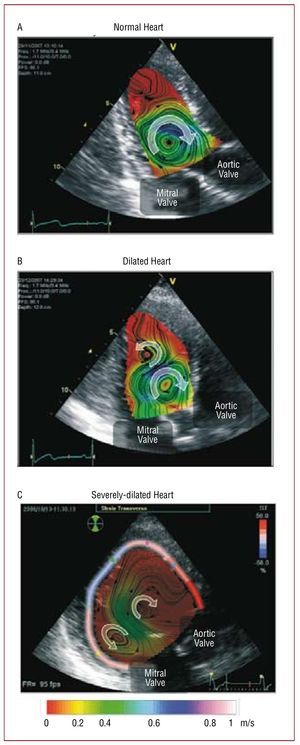

Experimental studies based on phase-contrast MR (PCMR)154-157 and echocardiography,158-163 have described the complex flow patterns inside the human left ventricle (LV). Figure 10 illustrates these patterns by displaying a sequence of maps of blood velocity in a healthy volunteer during early diastole (panel A), late diastole (panel B), systole (panel C), and isovolumic relaxation (panel D). The blood velocity vectors were imaged in the apical 3-chamber view of the LV and the anatomical images overlaid. At the onset of ventricular filling, the main flow pattern is the mitral starting jet, which is flanked by 2 counter-rotating swirling regions. The latter are the traces of a ring of vorticity associated with the mitral jet, whose 3D-structure is shown in Figure 11A, where the red loop represents the vortex ring and the arrows represent blood velocity. This vortex soon loses its symmetry because the part that is more proximal to the LV wall quickly decays under the effect of viscous dissipation. As a result, the flow at the end of diastole is dominated by a large single swirling pattern that is located close to the tip of the anterior leaflet of the mitral valve (Figure 10B). The 3D organization of the flow at this stage of the cardiac cycle is shown Figure 11B. The swirling region in the LV grows in size during diastole and can still be observed during the early stages of systole (Figure 10C), although it decays soon after the beginning of ejection. Studies using numerical simulation164-137 and in vitro experiments168-171 have confirmed this behavior.

Our current understanding of the hemodynamic irregularities that occur in patients with altered diastolic function is beginning to benefit considerably from clinical pilot studies based on the non-invasive characterization of the LV diastolic vortex. Ishizu et al159 have found that the size of this vortex increases by approximately 2 factors in patients with pseudonormalized transmitral flow patterns. By comparing PCMR data from 17 normal LVs to 1 dilated ventricle, Bolger et al157 have concluded that the fraction of mechanical energy that is stored by the LV vortex may be lower in patients with dilated cardiomyopathy (DCM). More recently, Hong et al141 have shown that the strength, size and temporal pulsatility of the diastolic vortex are lower in patients with DCM than in healthy volunteers. Recent studies by one of our groups161-163 suggest that the hemodynamic irregularities observed in DCM patients may be caused by the slower loss of symmetry of the early diastolic vortex ring, as opposed to the rapid loss of symmetry observed in normal LVs (Figure 10 and Figure 11). The physical argument for this behavior is that the posterior part of the vortex ring is farther from the wall in a dilated LV than in a normal LV (Figure 11C). Therefore, this part of the ring is subject to less viscous dissipation and does not decay as rapidly as in a normal LV. This picture is supported by Figure 12, which shows blood velocity maps in 1 healthy human LV and 2 dilated ones during late diastole. These maps indicate that only 1 clockwise vortex corresponding to an asymmetric vortex ring remains in the healthy LV (Figure 11B). However, additional counter-rotating vortices corresponding to a symmetric vortex ring persist in patients with DCM (Figure 11C). Counter-rotating vortices have been associated with higher energy losses in numerical simulations.166 Furthermore, they oppose the efficient redirection of blood from the mitral valve to the aortic valve that occurs naturally in healthy hearts. Figure 12 suggests that the size and circulation of the abnormal vortex, relative to those of the physiological one, increase with the severity of the disease. These results have led us to hypothesize that altered flow patterns may cause higher power requirements during early ejection, thereby reducing the pumping efficiency of the LV.

Figure 12. 2D color-Doppler blood velocity mapping in 3 human left ventricles (LV) overlaid on anatomical B-mode apical long-axis images. (A) Normal ventricle, (B) dilated ventricle and (C) severely-dilated ventricle. The color shades indicate the magnitude of the velocity as coded by the color bar at the bottom of the image, and the black lines show the streamlines. The arrowheads indicate the direction of the flow. Panel C also shows the % transverse strain of the LV wall, color-coded according to the color bar on top right corner of this panel.